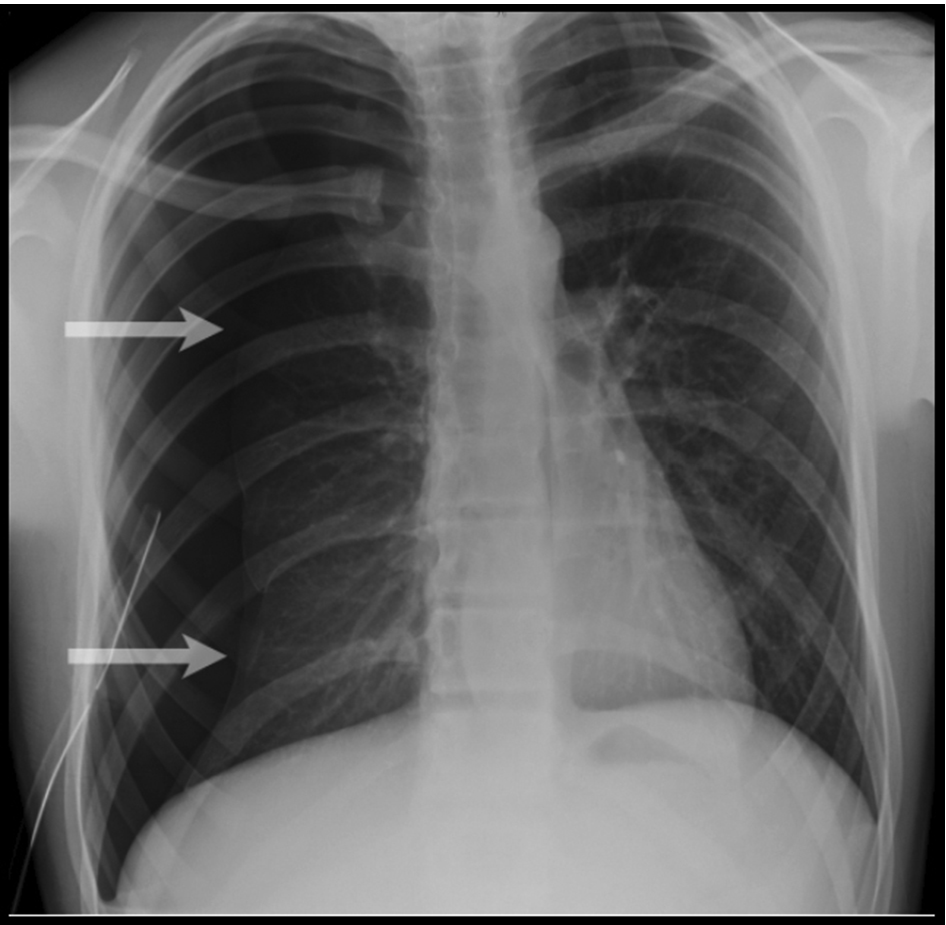

theRadiologist on Twitter "Male smoker in his 60s presents with cough Chest X Ray For Breathlessness dyspnea, commonly referred to as shortness of breath, is the subjective sensation of uncomfortable breathing comprised of various. seek medical help immediately if you are short of breath and you have chest pain, difficulty talking, wheezing or a fever, you. It can distinguish pneumonia from bronchitis and diagnose. It might feel like your chest is tight, you’re. Dyspnea,. Chest X Ray For Breathlessness.